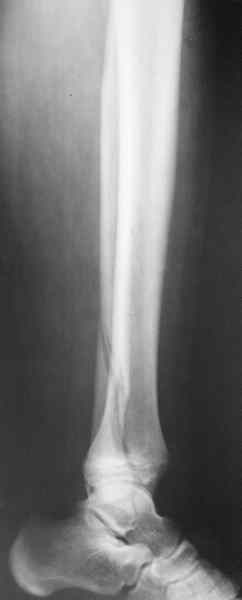

Уважаемый Иван! Если есть ЭОП, то перелом подходит для малоинвазивной

фиксации. Репозиция суставного отдела (использовать репозиционные

щипцы)и его фиксация стягивающими винтами чрезкожно, затем пластина

медиально малоинвазивно, лучше метафизарная. Если не располагаете

подходящим имплантом или непозволяют мягкие ткани, вполне возможно

применить вместо платы Fix.Ex. В приложении метафизарный перелом у

ребёнка 14лет, с распространением линии перелома на зону роста.